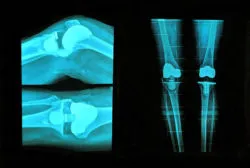

During knee replacement surgery, the natural joint is replaced with an implant to mimic movement. Damaged bone is typically removed to make way for the implant, which is secured with screws and bone cement. Bone cement is not always used to attach an implant, but it is a common strategy.

Knee replacement cement failure may cause a variety of side effects including aseptic loosening. Aseptic loosening typically occurs where an implant attaches to the tibia and involves the loosening of the implant without any accompanying infection. The side effect can occur due to fragmenting of the bone cement or because the bond between the bone and the cement is broken.

If implant loosening occurs, patients may have to undergo revision surgery. During revision surgery, a surgeon removes the previous implant and replaces it with a new implant. If bone and tissue have been damaged by knee replacement cement failure, the surgery may be longer and the surgeon may need to graft new bone to support the new implant.